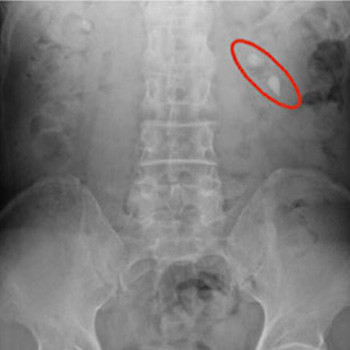

骨密度測定

腰椎および大腿骨頚部を直接測定することにより、骨の異変を早期に検知することができます。